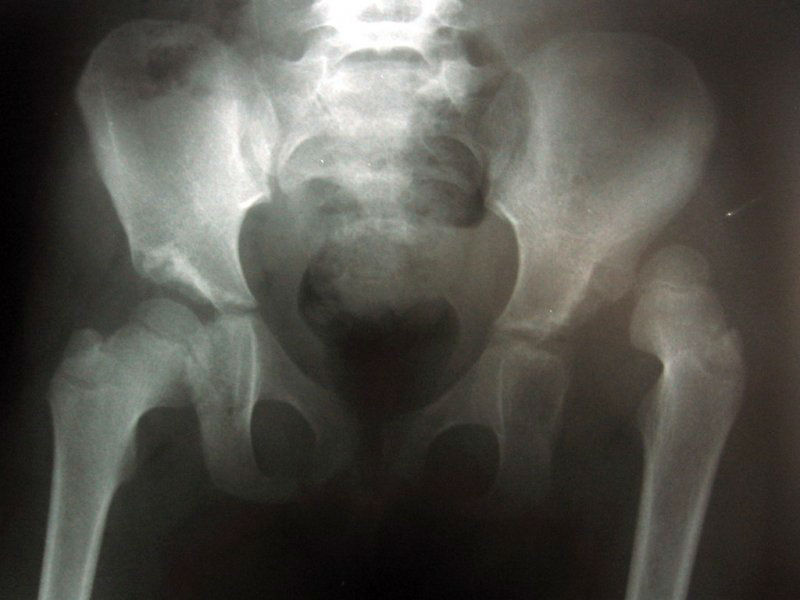

Перед началом лечения необходимо провести диагностику с использованием инструментальных методов. Например, рентгенография сустава в двух проекциях позволяет оценить степень повреждения. Если возникают сомнения в точности диагноза, врач-ортопед может назначить магнитно-резонансную или компьютерную томографию.